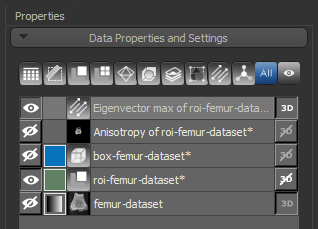

Two new items — a vector field and scalar-based anisotropy dataset — appear in the Data Properties and Settings panel after all computations are complete.

- Select the 3D vector map you created and make it visible in the 3D view by clicking the Eye icon in the Data Properties and Settings panel.

The 3D vector field-based anisotropy map appears in the 3D view at the default settings, with the vectors corresponding to the highest surface anisotropy colored yellow and those corresponding to the lowest, or isotropy, colored blue.

Information and settings related to the selected vector-based field appear in the bottom section of the Data Properties and Settings panel.